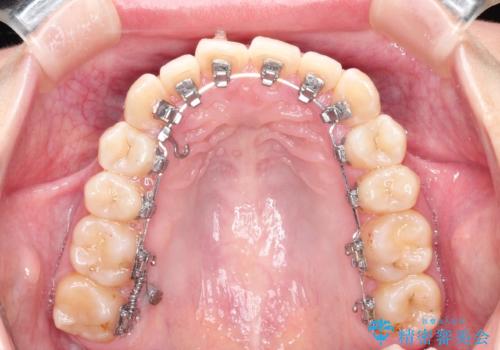

ハーフリンガル ワイヤー矯正による非抜歯・過蓋咬合の治療

- 非抜歯、大臼歯遠心移動による臼歯関係の是正・過蓋の改善をハーフリンガル・ワイヤー矯正にて計画した。